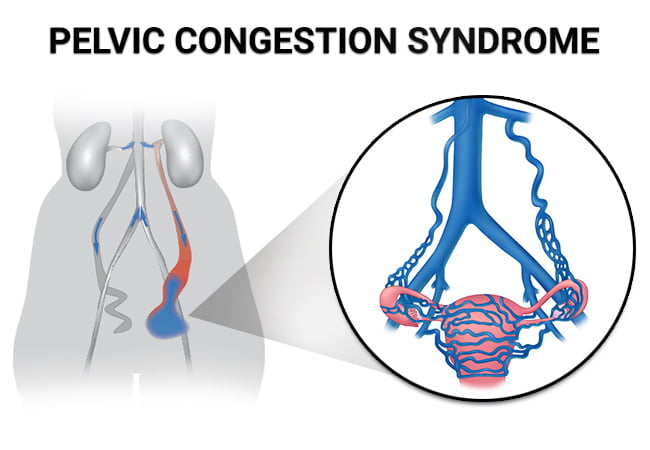

Pelvic Congestion Syndrome